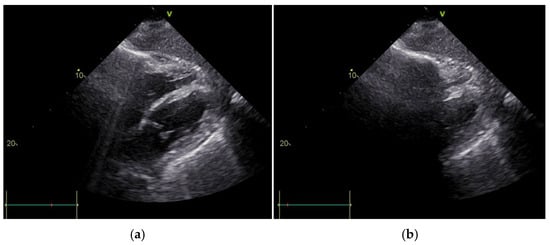

2. Case Report